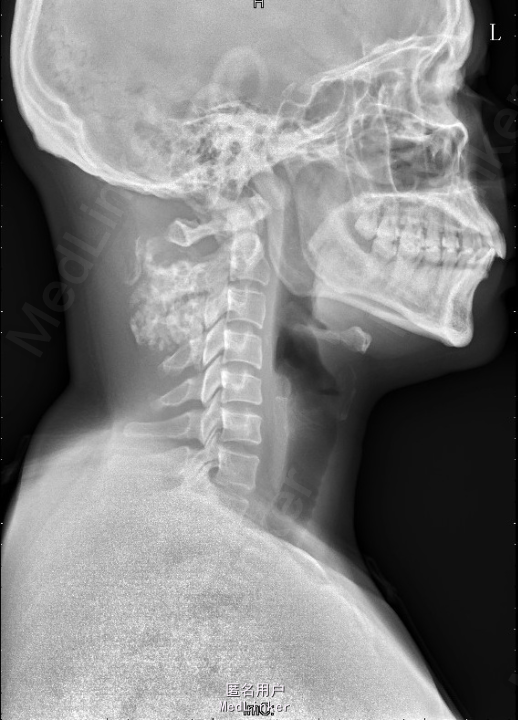

患者因“发现颈部包块5+年”入院。专科检查:左颈后见大小约5*6cm包块,质硬、边界欠清,无触痛。

辅助检查:颈椎正侧位片示:颈部左后份软组织内见多发片状稍高密度影,约C2、3椎体平面,与椎体附件结构分界不清,颈部MRI检查示:左颈后肌间隙肿块,大小约4.9*3.9*5.4cm,考虑肿瘤病变可能性大,其他待排。入院后积极完善相关检查,查CT示:约颈3-4平面左侧软组织内见类圆形混杂密度肿块影,最大截面约4.6x4.5 cm,内见多发不规则钙化灶,增强扫描见不均匀强化,局部与邻近附件骨质关系密切,局部皮质稍显毛糙,上述考虑肿瘤性病变可能